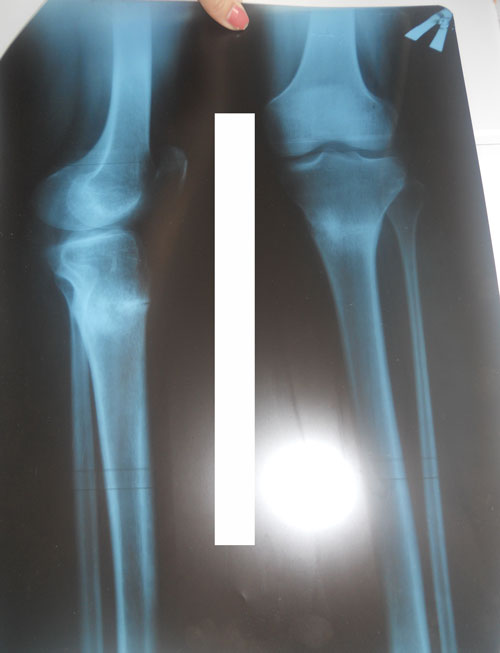

Дата операции 05.12.2013г.

Дата снятия аппаратов 20.02.2014г.

Срок лечения 75 дней.